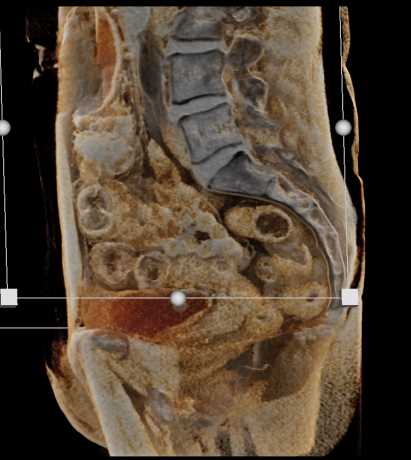

Urachal Carcinoma of the Bladder